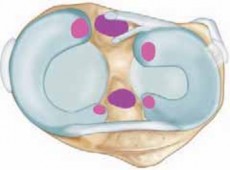

Chapter 34 Meniscal Repair Nicholas A. Sgaglione and Michael J. Angel DEFINITION A meniscus tear results in m…